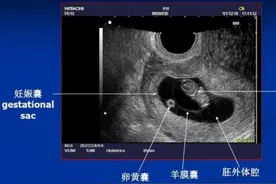

在了解怀孕时间的推算方式时,我们的先知道孕期的周期,一般时怀孕10个月,还有妊娠月就是28天。女性最后一次月经的第一天算起,经过了280天就是我们的怀孕孕期。女性分娩的时间一般是40周左右。在这个期间分娩的胎儿,一般是足月分娩。